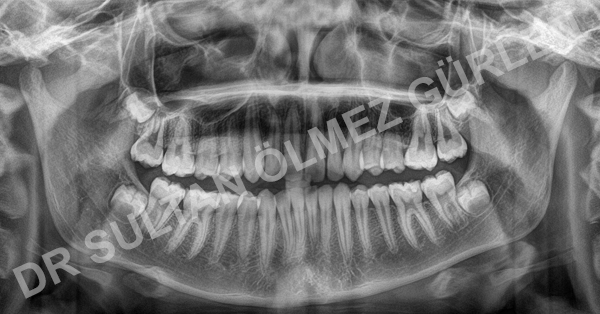

Orthodontic treatment is not only limited with children but also adults can have their teeth straightened. One of every five patients in our clinic is over 21. Adult orthodontics improve dental health, personel appearance and self esteem as well. Crowded teeth, spacing between teeth, improper bite can cause gum and underlying bone damage, gingival recession and tooth cavities.

Adult orthodontics can be used at any age if gum, underlying bone structures are healthy. Periodental problems can cause limited tooth movement. In addition, some treatment procedures need growth pattern. Adult patients can have limited treatment options cause they are non-growers any more.